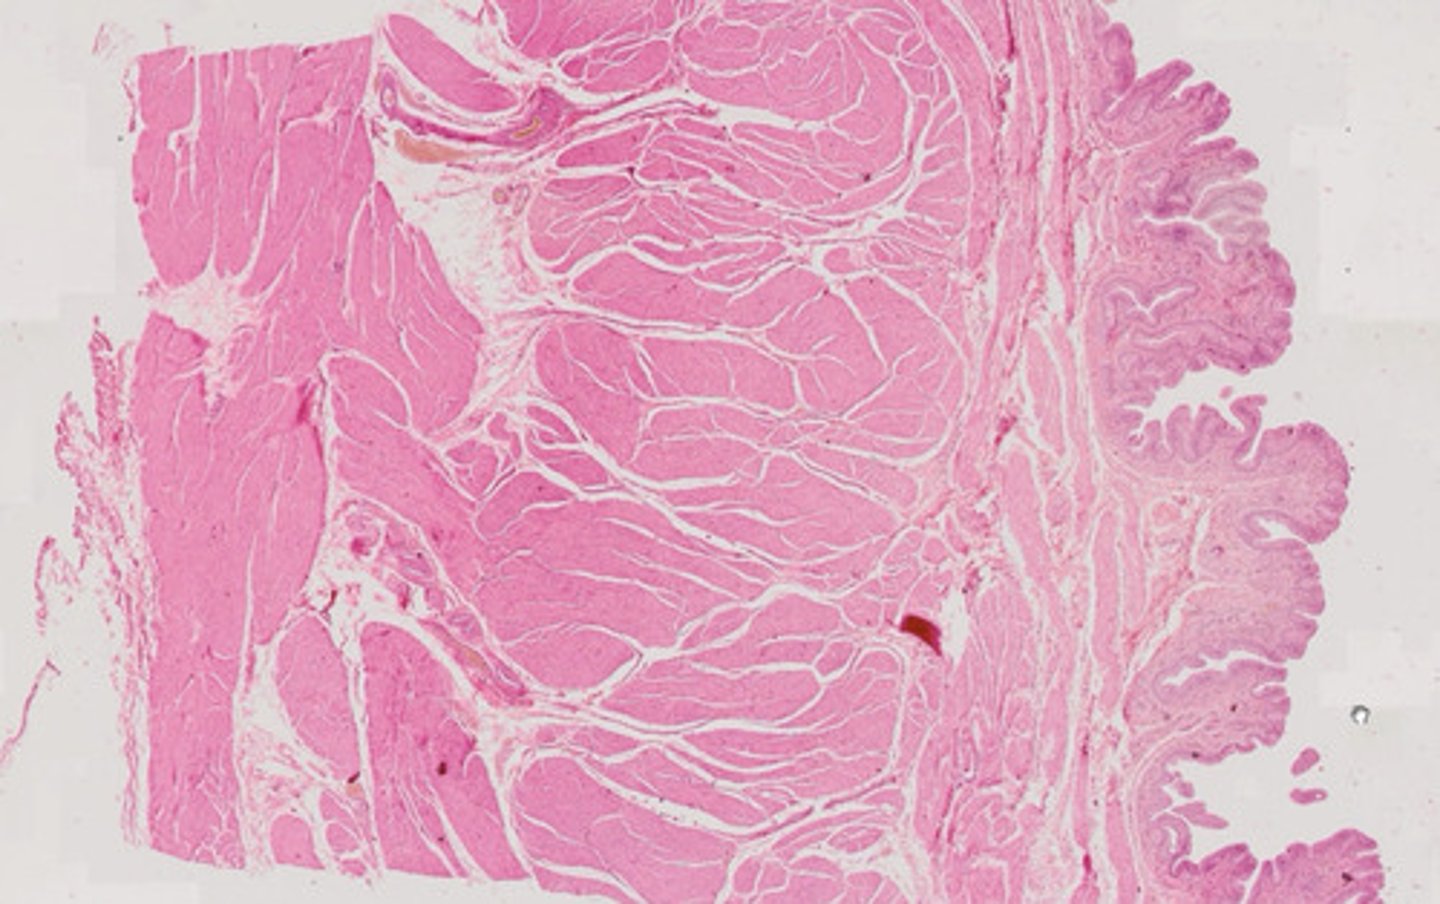

Przełyk (H+E)

Macica (H+E)